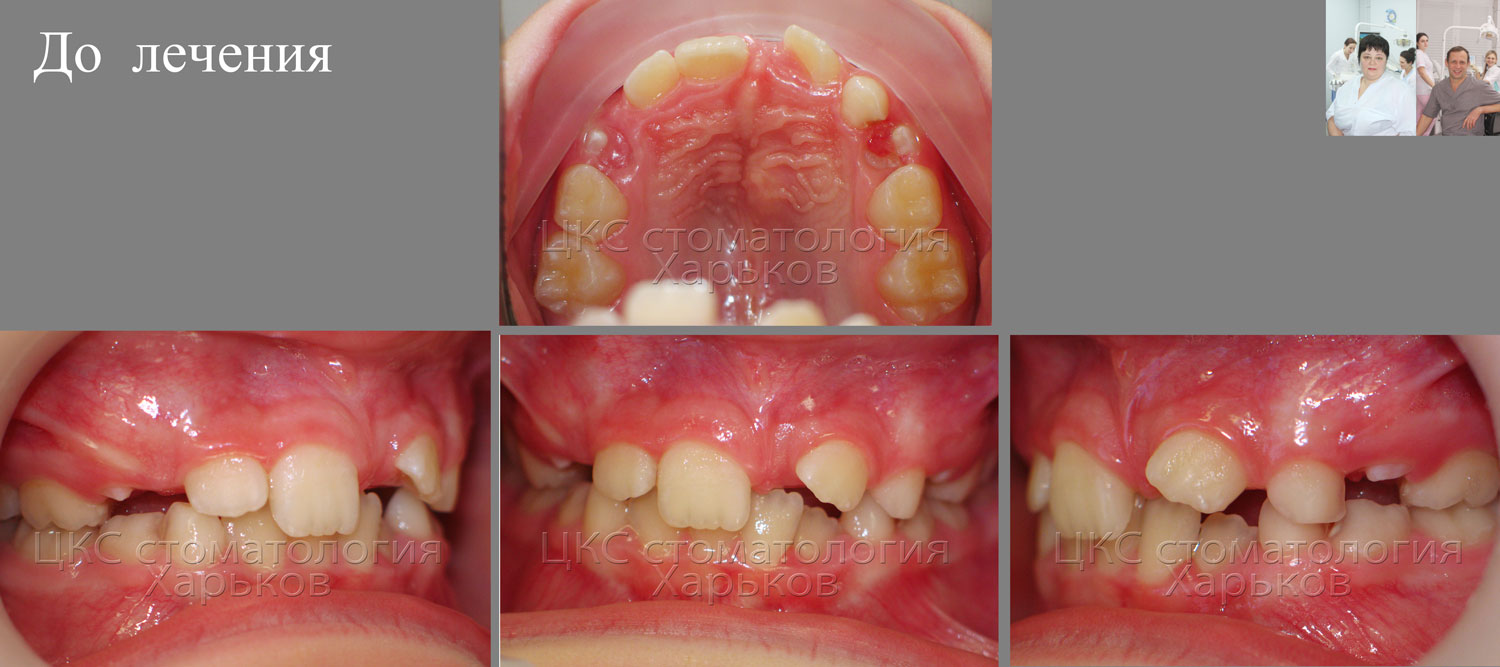

| Сверхкомплектные плюс ретенированный зубы. До лечения. |

Что заставило пациентов обратиться к стоматологу? Неровные зубы. И задержка прорезывания центрального резца верхней челюсти слева. Других симптомов нет. Чтобы выяснить причины возникших проблем назначаем панорамный снимок.

| Зубной ряд пациента до лечения |

Очевидно, что существует дефицит места зубного ряда.

| Дефицит места зубного ряда |

Не хватает места зубам 21 (центральный резец), и двум клыкам ( зубы 13 и 23).

| Прикус пациента со сверхкомплектными зубами, до лечения |